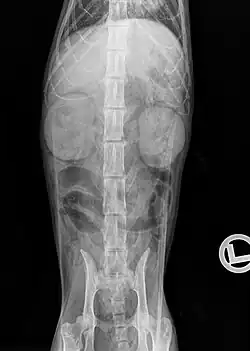

An X-ray examination can be used to detect changes in the size, density and position of the kidneys as well as some urinary stones (struvite and calcium oxalate stones are "radiopaque") and soft tissue calcifications. In severely emaciated cats or fluid accumulations in the retroperitoneal space, however, the kidney can only be visualized to a limited extent on the X-ray image due to the resulting reduction in contrast. Excretory urography, in which a radiopaque contrast medium (e.g. Iopamidol, Iohexol) is injected into the bloodstream and its excretion via the kidneys is recorded radiographically. This makes it possible to detect circulatory disorders, dysfunctions of the renal corpuscles and obstructions of the outflow pathways.[22]